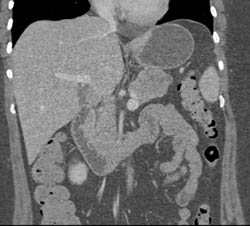

Diagnosis

Intraductal Papillary Mucinous Neoplasm (IPMN)